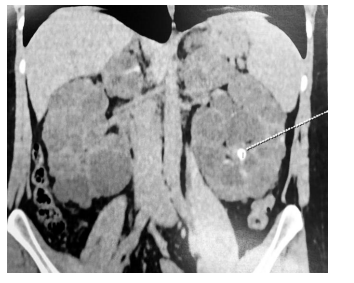

Observe a imagem de tomografia computadorizada a seguir.

A partir da imagem, e correto concluir que o diagnóstico é